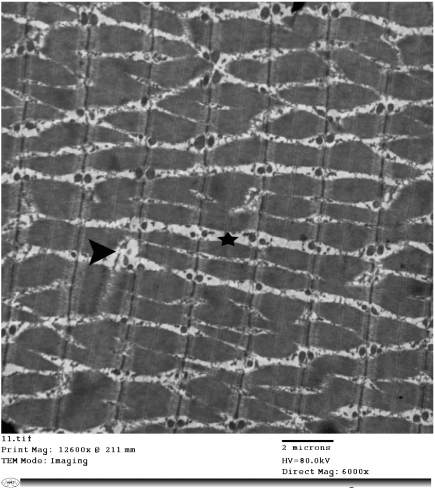

| Figure 20: Electron micrograph of a skeletal muscle of a vitamin E-treated rat with relatively normal pattern and arrangement of the myofibrils and decreased intermyofibrillar space (star). Note: focal area of degenerated myofibrils (arrow head). X60000. |